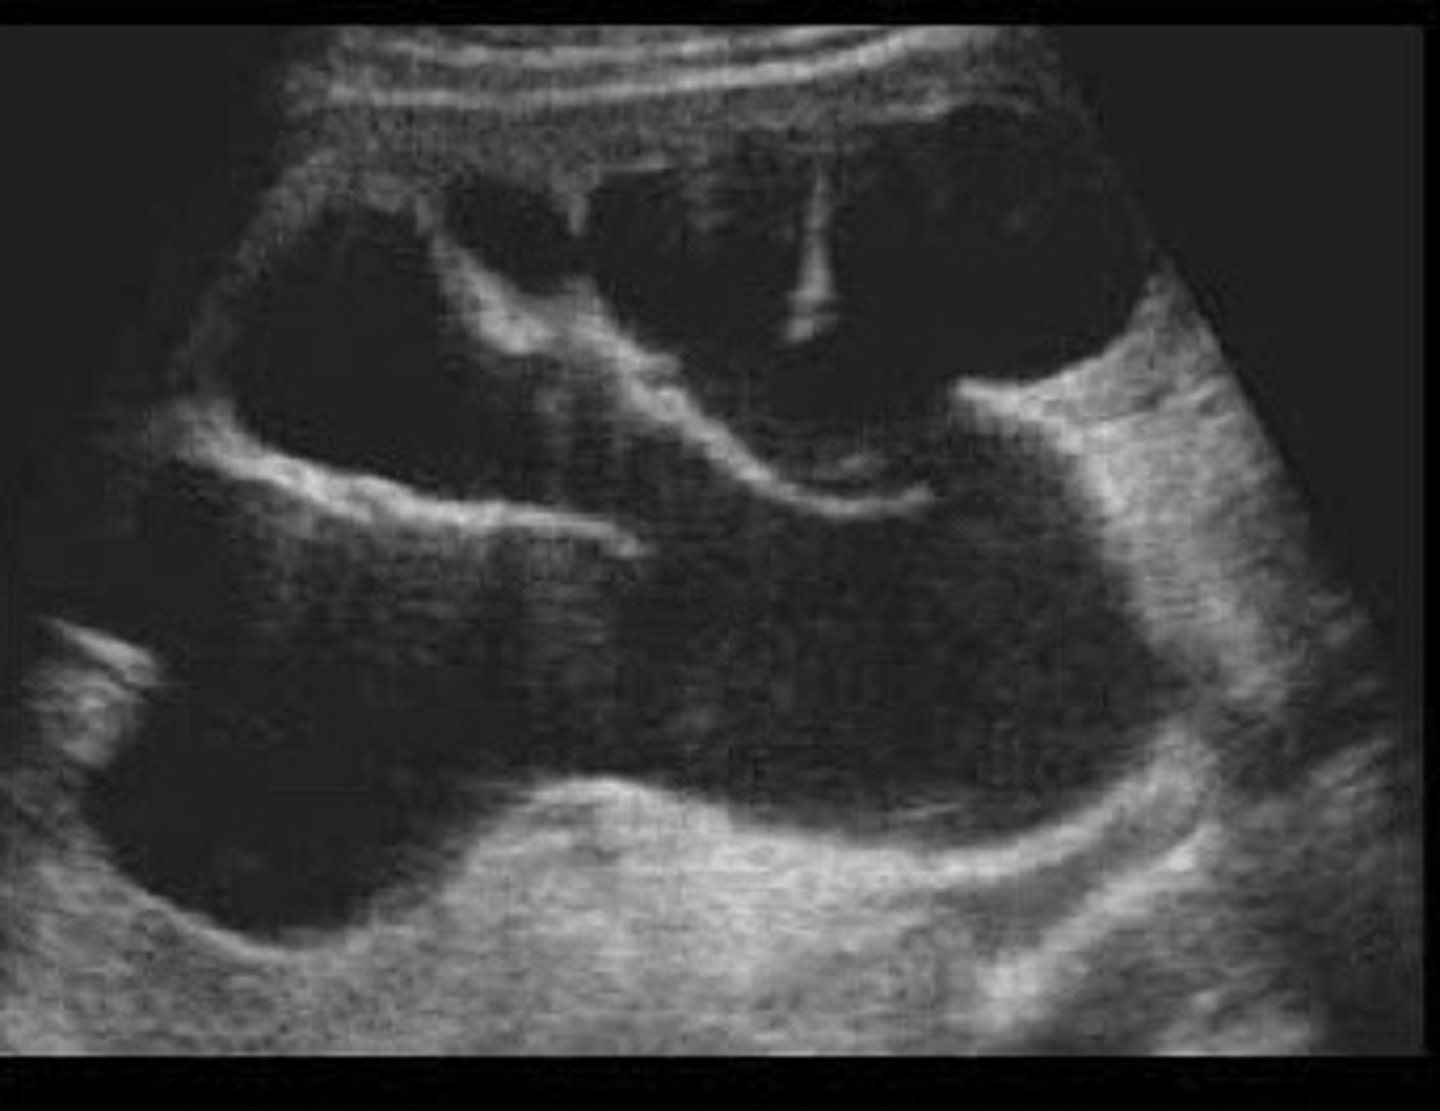

Staghorn calculi

What does this image show

Calcifications filling all or most of the renal collection system/calyces

What is staghorn calculi